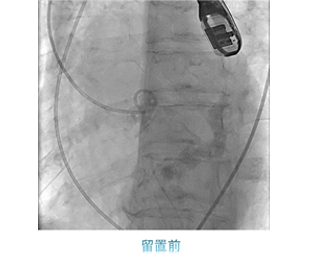

一方治療には、狭くなった冠動脈にステントを留置する冠動脈ステント留置術(PCI)をはじめ、心臓以外の動脈や静脈を拡張させる血管拡張術(PTA)、頻脈性不整脈の原因となる電気回路を遮断させるため、心筋に高周波電流を流して焼灼するアブレーションや、徐脈性不整脈に対するペースメーカー埋込術(PMI)、除細動器のデバイス埋め込み術(ICD)などがあります。